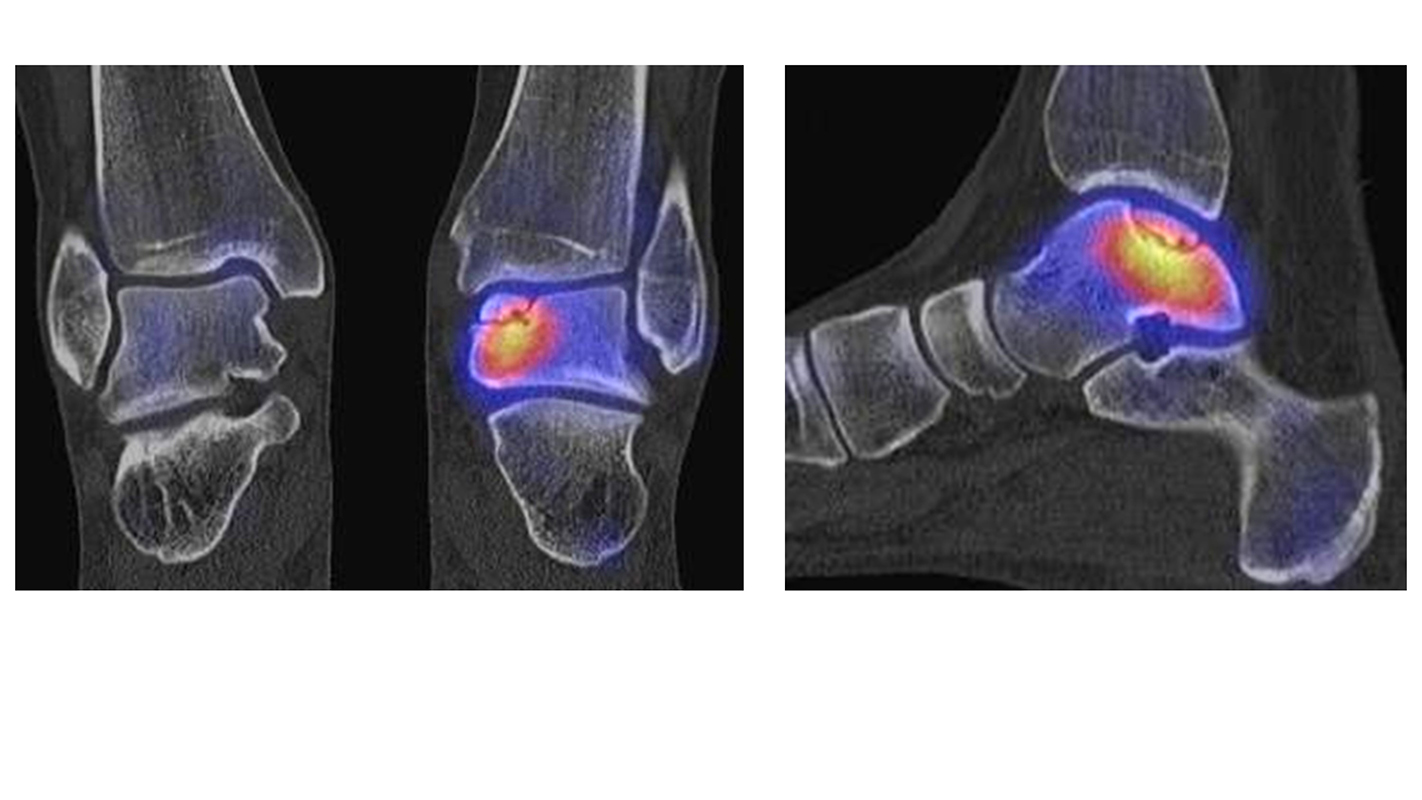

Osteonekrosen

Abbildung 9.2.a bis d: SPECT/CT zur Beurteilung der Knochen-Vitalität bei einer Talusnekrose. 5 Jahre zuvor während der Arbeit war die Patientin beim Treppensteigen umgeknickt und zog sich Außenbandrupturen zu. Nachfolgend persistierende Beschwerden mit Entwicklung einer Talusnekrose. Frage nach Vitalität und Ausdehnung der Nekrose. Deutliche bis intensive Traceranreicherung im Bereich des linken Talus. Im SPECT/CT befindet sich der Hypermetabolismus in allen Abschnitten des Talus mit relativer Aussparung eines sich demarkierenden Fragmentes lateral, was die laterale Talusschulter umfasst, die Größe beträgt transversal ca. 23 x 16 mm. In diesem Fragment relativ homogene Skelettstruktur, diese Befunde weisen auf eine trophische bzw. nekrotische Störung des Talus hin mit einem sich demarkierendem Fragment, welches die laterale Talusschulter beinhaltet.

Die Abbildung 9.3.a bis d zeigt ein weiteren Fall mit einer SPECT/CT zur Beurteilung der Knochen-Vitalität bei einer Talusnekrose. Die Bilder zeigen eine abgelaufene Nekrose mit zystischen Resorptionen des linken Talusdoms bei nachweislich erhaltener Vitalität der umgebenden Knochenabschnitte aufgrund des hier überall deutlich erhöhten Knochenmetabolismus (= inkomplette Restitutio). Aufgrund der nachweislich erhaltenen Vitalität konnte erfolgreich eine Knochen-Transplantation erfolgen.Deutlich geringer ausgeprägte nekrotische Veränderungen auch im rechten Talusdom bei hier weitgehend erhaltenen Gelenkkonturen.